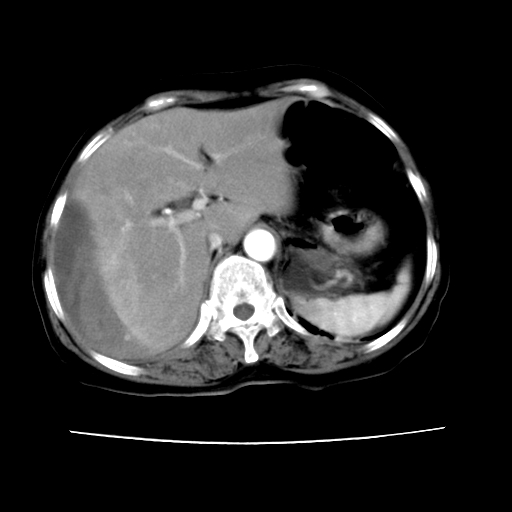

2008-11-10ct平扫(其间去中山医院诊治未行特殊治疗)

2008-11-10ct平扫见并肝内、血膜下血肿基本吸收,肝内低密度灶缩小。此时再做增强ct应有显着意义。对患者/医者都好!

从平扫+增强及治疗后复查片,病变明显缩小,不考虑肝癌出血可能,还是考虑为良性病变可能性大;单纯血肿并包膜下积液吧,病变强化没法解释,肝血管破裂出血吧,增强不符合典型血管瘤的表现,良性肿瘤破裂出血吧,复查片看来好像也不太支持(没做强化也不太好说)。本人还是考虑单纯肝内血肿并包膜下积液,强化是不是血管有外渗。

患者自6月至11月,如果是肝癌,没有经过特殊治疗,想必应该会有所进展吧,而不是ct所见,反而似有病灶减小的趋势。建议增强。

追问病史,患者有过度用力病史,当时立即感腹痛;所以还考虑肝破裂可能性大。